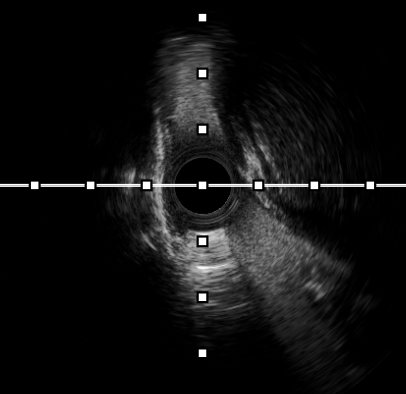

手术在神经内一科副主任胡军和刘军主任医师指导下进行,贾瑞华副主任医师主刀,介入导管室、麻醉科等多学科团队紧密协作。术中,通过股静脉穿刺,将导管送入狭窄的静脉窦内,在血管内超声(IVUS)指导下精准测量狭窄段的长度和直径后,将支架顺利释放并展开,成功覆盖狭窄部位。术后即刻造影显示,狭窄的静脉窦完全开通,血流恢复正常,患者术后恢复良好,头痛和视力模糊的症状消失,术后第3天顺利出院。